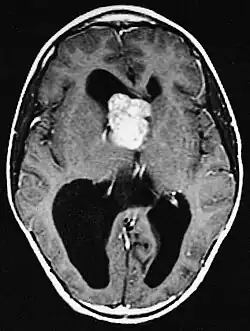

Subependymal giant cell astrocytoma (SEGA, SGCA, or SGCT) is a low-grade astrocytic brain tumor (astrocytoma) that arises within the ventricles of the brain.[1] It is most commonly associated with tuberous sclerosis complex (TSC). Although it is a low-grade tumor, its location can potentially obstruct the ventricles and lead to hydrocephalus.

Diagnosis is made by imaging with a contrast-enhanced MRI or CT scan of the brain.